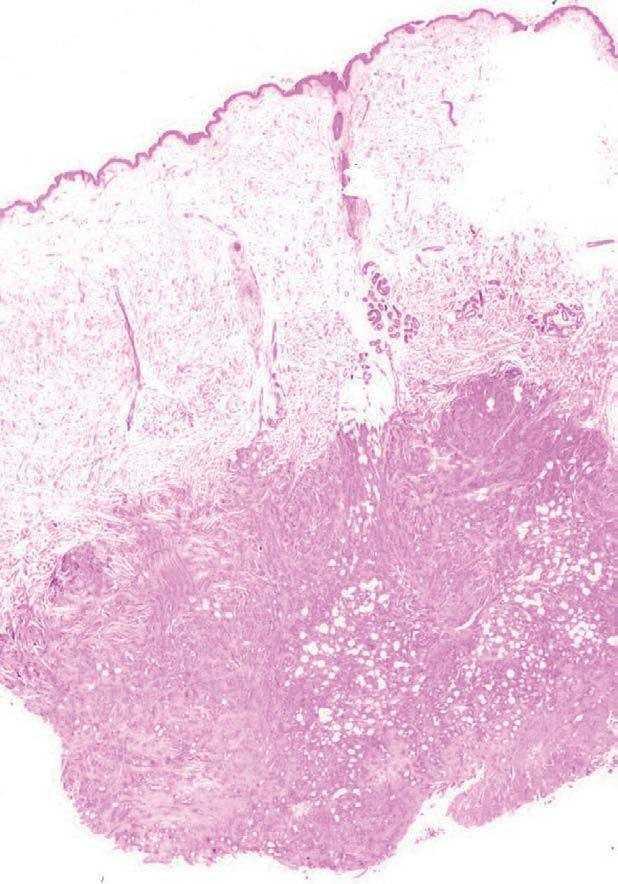

El estudio anatomopatológico de una biopsia realizada en la lesión nodular epigástrica destacó una proliferación celular densa a nivel de la dermis profunda y del tejido celular subcutáneo que respetaba la epidermis y los anejos cutáneos (fig. 2), constituida por células epiteliales dispuestas siguiendo un patrón glandular moderadamente bien diferenciado (fig. 3). Con técnicas de inmunohistoquímica estas células tumorales mostraron una clara positividad para antígeno carcinoembrionario (CEA) (fig. 4) y una negatividad para receptores estrogénicos (fig. 5).

Fig. 2.--Estudio histopatológico que demuestra una proliferación celular densa en la dermis profunda y en el tejido celular subcutáneo, sin afectar a la epidermis y a los anejos cutáneos (H&E, x 10).